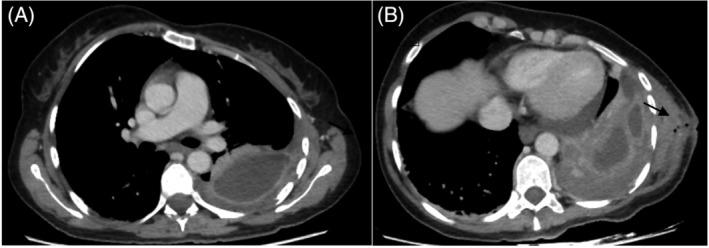

Empyema necessitans: After recent thoracostomy in an immunocompromised patient.

This paper consists of a clinical image of an unexpected complication of a pleural space infection that dissects through the pleura into the soft tissues of the chest in an immunocompromised patient.